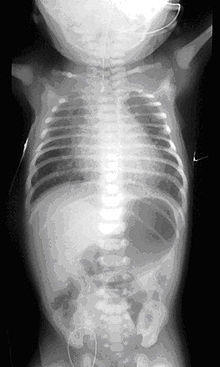

Plain X-ray of the chest and abdomen showing a feeding tube unable to move beyond an upper esophageal pouch.

On plain X-ray, a feeding tube will not be seen pass through the esophagus and remain coiled in the upper oesophageal pouch.[3]

If any of the above signs/symptoms are noticed, a catheter is gently passed into the esophagus to check for resistance. If resistance is noted, other studies will be done to confirm the diagnosis. A catheter can be inserted and will show up as white on a regular x-ray film to demonstrate the blind pouch ending. Sometimes a small amount of barium (chalk-like liquid) is placed through the mouth to diagnose the problems.